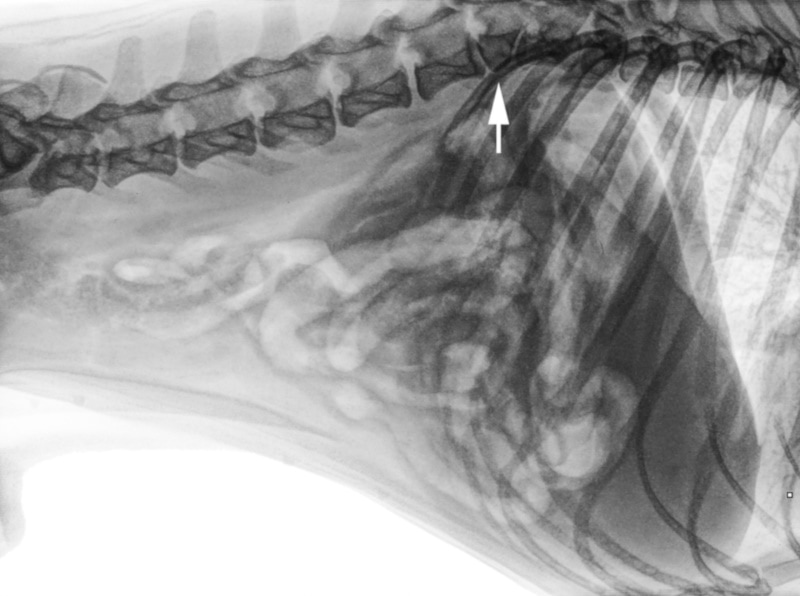

Due to the screw in their tail, some pugs experience spinal problems. Hemivertebrae are abnormally formed spinal bones present from birth; they can be wedge-shaped or fused together. Hemivertebrae may or may not cause issues. Some dogs live problem-free with hemivertebrae, whereas others experience compression of the spinal cord, causing pain and weakness. Diagnosis of this condition requires some form of imaging study. X-rays are a good starting point and can be performed at most general practice clinics, but CAT scans may be required.